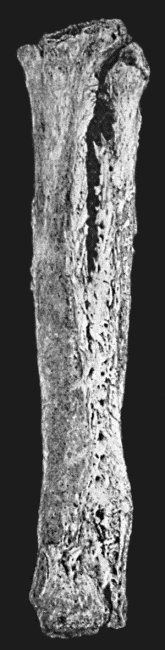

125.Tuberculous Disease of Tibia 457

31.Actinomycosis of Maxilla 128